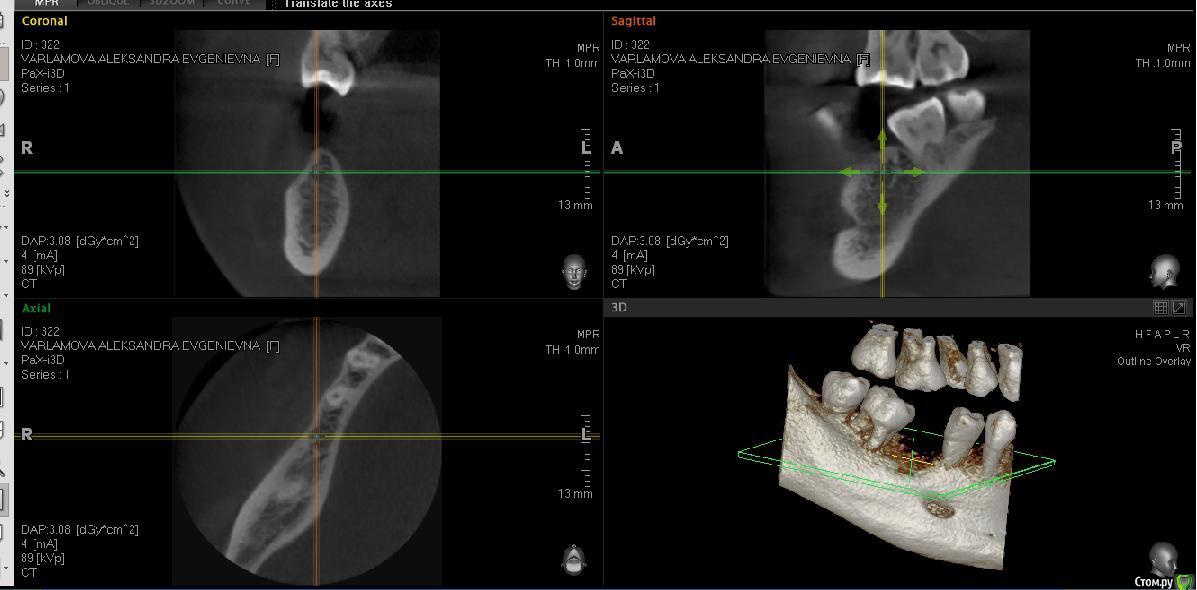

Александра_85 Опубликовано 12 марта, 2015 Поделиться Опубликовано 12 марта, 2015 (изменено) Здравствуйте, собираюсь сделать имплантацию 6 нижнего зуба справа.Удален этот зуб был 4 года назад, кость довольно сильно ушла.Мой имплантолог советует кость не наращивать, и установить тонкий импрант АльфаБио.Хотелось бы услышать ваше мнение.Во вложении ортопантограмма годичной давности, и свежее КТ по ссылкеhttp://www.fayloobmennik.net/4686662 Я не очень понимаю, как выложить срез.Сделала скрин, может по нему будет понятно Изменено 12 марта, 2015 пользователем Александра_85 Ссылка на комментарий

red_butler Опубликовано 12 марта, 2015 Поделиться Опубликовано 12 марта, 2015 поставьте перекрестье, так как я нарисовалhttp://s011.radikal.ru/i315/1503/ac/4140dbf1399c.jpg Ссылка на комментарий

Александра_85 Опубликовано 12 марта, 2015 Автор Поделиться Опубликовано 12 марта, 2015 поставьте перекрестье, так как я нарисовалhttp://s011.radikal.ru/i315/1503/ac/4140dbf1399c.jpg поставьте перекрестье, так как я нарисовалhttp://s011.radikal.ru/i315/1503/ac/4140dbf1399c.jpgСпасибо, что помогаете. Ссылка на комментарий

Александра_85 Опубликовано 12 марта, 2015 Автор Поделиться Опубликовано 12 марта, 2015 да, пожалуйста, ждем снимокВот. Ссылка на комментарий

red_butler Опубликовано 12 марта, 2015 Поделиться Опубликовано 12 марта, 2015 (изменено) Вот.я бы имплантировал с одномоментной костной пластикой, однако существует современная тенденция - ставить импланты малого диаметра и ограничиваться пластикой десны Изменено 12 марта, 2015 пользователем red_butler 1 Ссылка на комментарий